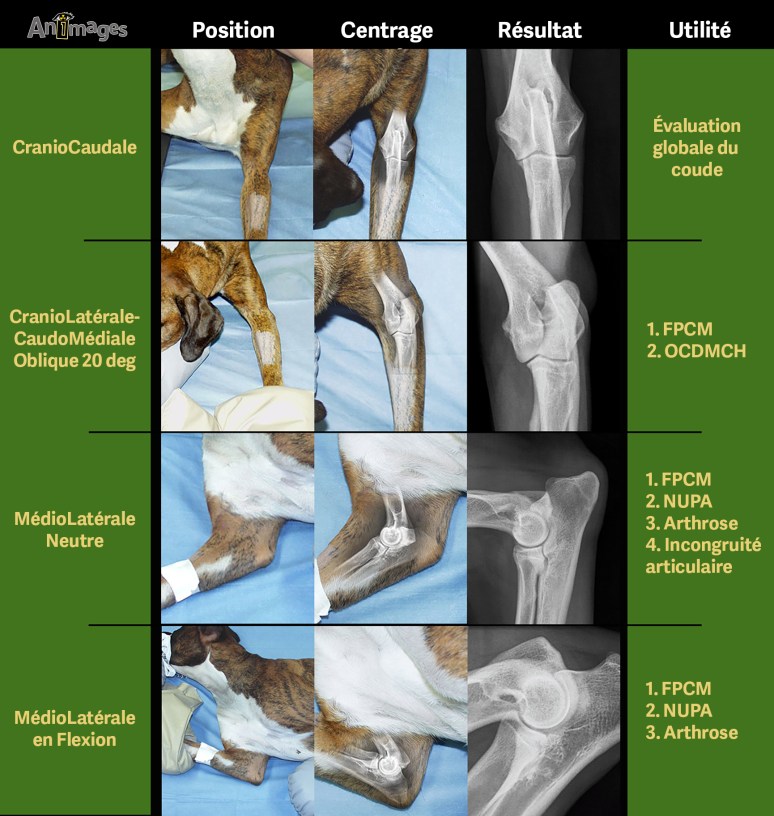

Parce que la dysplasie du coude regroupe diverses entités lésionnelles parfois associées (NUPA, FPCM, incongruité articulaire et OCD) et qu’il s’agit d’une articulation complexe, l’examen radiologique complet doit inclure des projections multiples, chacune avec un objectif particulier [1]. Les incidences supplémentaires (en plus des deux projections orthogonales standards) permettent de désuperposer certaines régions anatomiques pour mieux les évaluer. Les projections additionnelles classiques sont la médiolatérale en hyperflexion ainsi que la craniolatérale-caudomédiale oblique (CrL-CdMO) permettant de mettre en évidence respectivement le processus anconé et le processus coronoïde médial (PCM), deux structures fréquemment impliquées dans les dysplasies du coude. La distomédiale-palmarolatérale oblique (DiM-PLO) est une autre incidence qui permet aussi d’évaluer le PCM [2] mais sa réalisation est plus complexe.

La figure suivante de Guy Beauregard illustre le positionnement du patient permettant d’obtenir les incidences mentionnées ci-dessus.